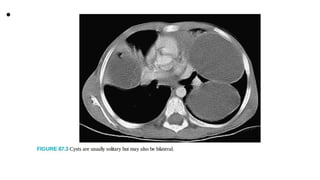

• About 75% of infected individuals develop one or more cysts in the liver,

and the right lobe of the

liver is affected more often than the left.15 Cysts may also develop in the

lungs, kidneys, spleen, brain, and

musculoskeletal system. In most of the reported series, the lower lobes of

both lungs are affected more

often than the upper lobes.16 Cysts are usually solitary but may also be

bilateral 19 When the